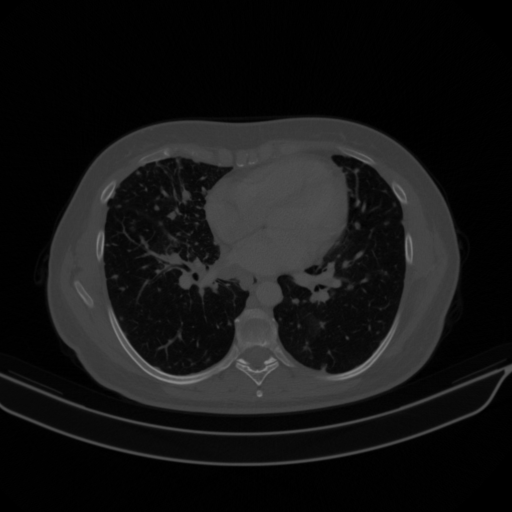

Original VENOUS CT scan

Full window (WL 1023.5, WW 4095 β†’ Low βˆ’1024, High +3071)

Lung window (WL -600, WW 1500 β†’ Low βˆ’1350, High +150)

Mediastinum window (WL 40, WW 400 β†’ Low βˆ’160, High +240)